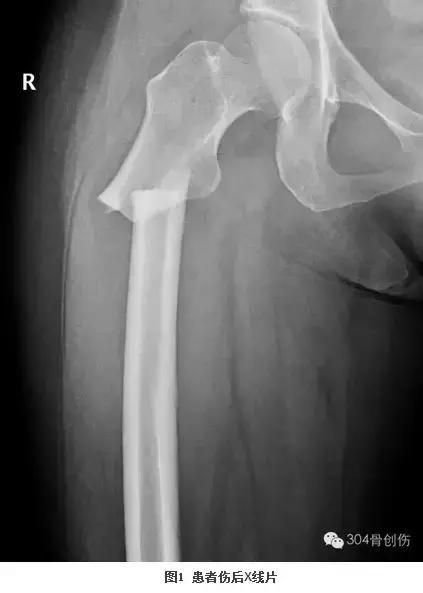

大查房见到一女性病人,57岁,洗澡时地滑导致股骨粗隆下骨折。粗隆下骨折多见于青壮年高能量外伤后,而眼前的病人是一位白净的中年女性,仅仅是洗澡过程中骨折,按说致伤能量不是很高,当时首先想到的是肿瘤骨转移的病理骨折,反复查看X线片和CT后不符合肿瘤骨转移病理骨折。王晓宁主诊医生再次补充病史:患者因内科疾病长期服用激素。服用激素能够导致骨坏死和骨质疏松,骨坏死常见于股骨头,骨质疏松骨折多见于股骨近端。带着疑问全科医生仔细阅读影像资料料,此例粗隆下骨折表现的仅是简单骨折(图1),而经典的粗隆下骨折多是粉碎或长螺旋形(图2、3)。全科医生畅所欲言,充分发表各自看法,却不能完美解释上述疑问,按现有医疗水平处理此类骨折不是难事,但解除不了内心的疑惑。经过激烈讨论后,决定暂缓手术、寻找证据、明确骨折原因。大家分头查找文献,两天后再次讨论。